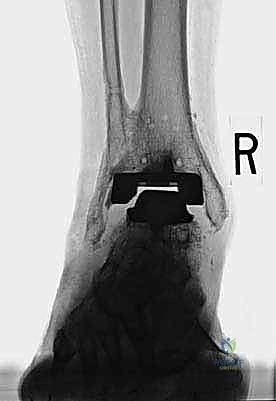

TECH FIG 1 • (continued) Two guidewires are placed across the fracture site ( B ) within the substance of the medial malleolar bone.

"Okay, guidewires are in place, reduction is solid. Now, we'll use cannulated screws for percutaneous fixation. This allows us to maintain our guidewire position, which is critical. Let's measure for screw length over the guidewire. Take your time, get the exact measurement. We want bicortical purchase in the distal tibia without violating the far cortex or the anterior neurovascular structures. Once measured, I'll pre-drill over the guidewire, then tap if necessary, and finally, insert the cannulated screw. Feel that compression as the screw engages? Excellent. Repeat for the second guidewire. Alternatively, if we preferred solid-core screws, we would drill over the guidewire, then withdraw the guidewire, and place the solid-core screw. But cannulated is often easier here. Let's get a fluoroscopic shot to confirm position and compression."

TECH FIG 1 • (continued) Firm compression is achieved ( C ) across the fracture site.